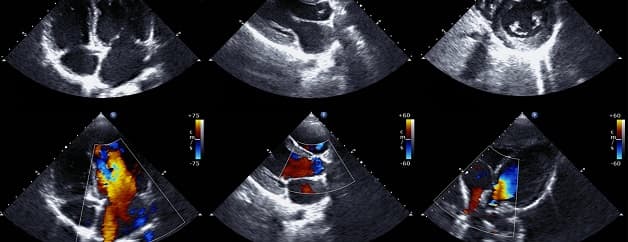

Thông liên nhĩ là một dị tật bẩm sinh ở tim. Để chẩn đoán chính xác bệnh, các bác sĩ phải tiến hành nhiều xét nghiệm, trong đó có các phương pháp siêu âm tim thông liên nhĩ. Hiện nay, siêu âm tim xác định thông liên nhĩ bẩm sinh bao gồm các kỹ thuật như siêu âm Doppler tim, siêu âm qua thực quản và siêu âm cản âm.

Siêu âm tim Doppler là một kỹ thuật hình ảnh dùng để đánh giá kích thước lỗ thông liên nhĩ cũng như định hướng phương pháp điều trị thích hợp.

Kỹ thuật cũng được dùng để phác thảo các cấu trúc của tim, các buồng, van của tim và các mạch máu chính lân cận. Nó cũng giúp bác sĩ có thể hình dung và phân tích các chuyển động của mô tim và lưu lượng máu. Nhờ siêu âm tim Doppler, lượng máu chảy, tốc độ, hướng đi và những bất thường có thể xảy ra ở trái tim được phát hiện.

Trên siêu âm tim Doppler, bác sĩ có thể xác định được vị trí, kích thước lỗ thông liên nhĩ, chiều shunt, áp lực động mạch phổi, sự liên quan giữa lỗ thông và các bộ phận xung quanh. Từ đó đánh giá mức độ thông liên nhĩ của người bệnh và có hướng điều trị phù hợp.

Siêu âm tim xác định thông liên nhĩ bẩm sinh bao gồm các kỹ thuật Doppler tim, siêu âm qua thực quản và siêu âm cản âm